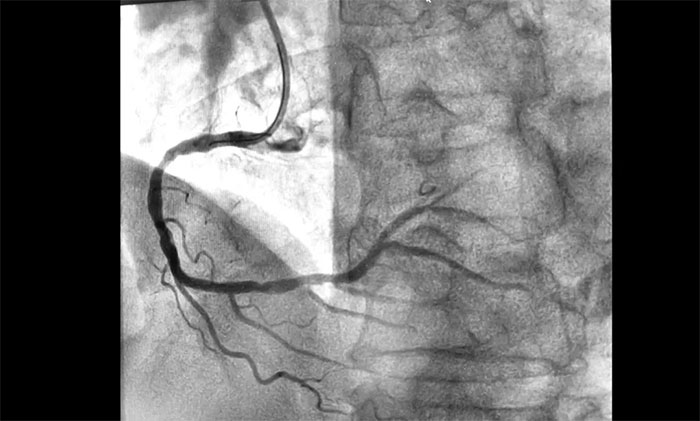

近日,上海蓝十字脑科医院为一名急性心梗患者实施介入手术。该患者因“间断心前区不适伴咽部束缚感7小时,全身乏力3小时”入院,综合其病史和相关检查确诊其为急性下壁心肌梗死,随时有猝死风险,手术指征明确。经球囊扩张和支架置入,开通闭塞血管,助其恢复心肌供血。

▲ 术后,血管顺利开通